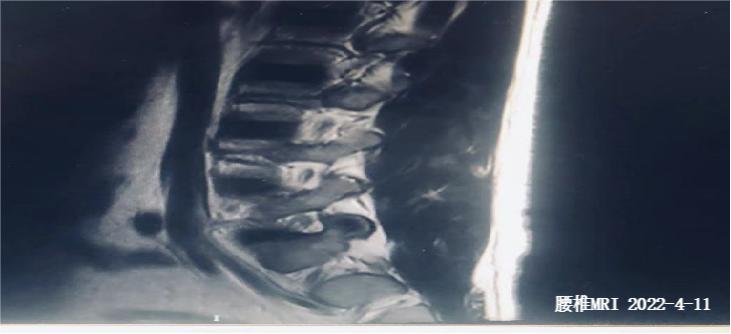

影像学检查

腰椎MRI平扫:L4,5棘突骨水肿伴棘间韧带炎;

(腰椎MR)